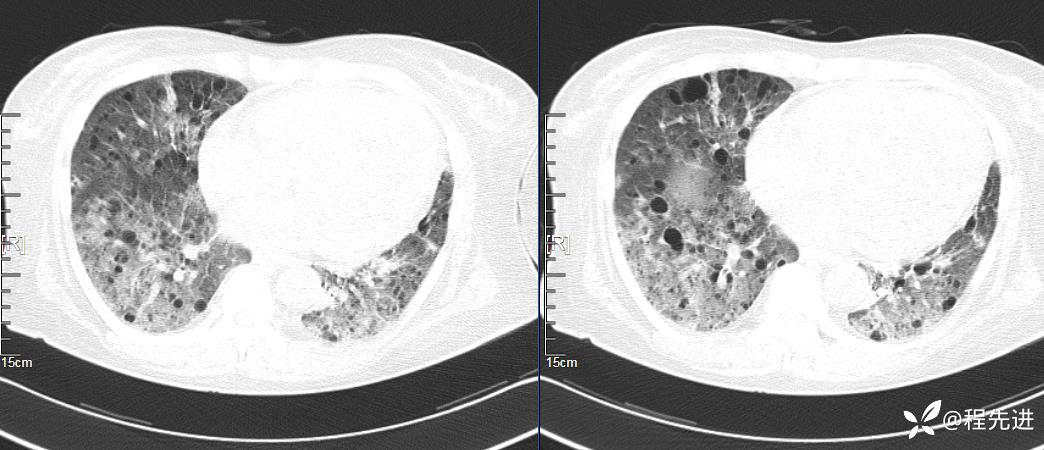

简要病史:胸闷、气促、进行性呼吸困难5年,双下肢浮肿、恶心呕吐1周

CT平扫(纵隔窗无特殊,就不上传了):

1、两肺弥漫性肺气囊的鉴别诊断有哪些?

2、本例肺气囊分布有什么特点?肺气囊有无小叶核心?有没有间质纤维化及伴发结节?